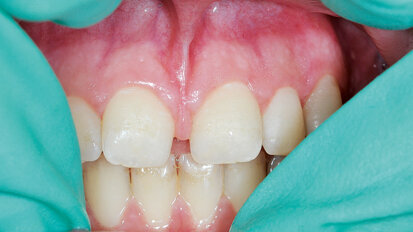

Align Technology G8